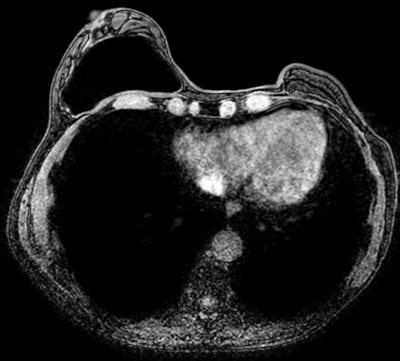

MRI can reliably reveal collapsed intracapsular rupture by detecting shell fragments floating inside the silicone gel implant ("linguine sign"). This sign is often associated with extracapsular rupture. An uncollapsed silicone implant rupture may be seen as a subtle silicone invagination between the inner shell and fibrous capsule, known as the "teardrop sign" or the "keyhole sign." Other imaging signs, such as the "salad oil sign" or "droplet sign," are nonspecific and not reliable without other MRI evidence of implant rupture, but these signs should prompt a search for subtle signs of intracapsular rupture, according to Juanpere.

Multiplanar dedicated T1- and T2-weighted MRI techniques are used for evaluating implant integrity. He does not recommend the use of contrast agents in MRI studies for assessing breast implant integrity, but when the priority is detecting recurrence or residual tumors, contrast-enhanced MRI of the breast is useful for characterizing parenchymal lesions. He favors magnets of at least 1.5 tesla because of the ability to use MR sequences that can more readily suppress or emphasize the signal from water, fat, or silicone. Turbo spin-echo T2-weighted images, short-time inversion recovery silicone excited (silicone hyperintense, water-suppressed), and silicone-saturated (water hyperintense, silicone-suppressed) are the most important sequences in silicone breast implant assessment.